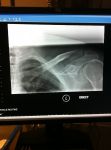

Out for a nice afternoon training ride today when disaster hits....Windy+reaching for water bottle equals crash.

Finished another 5km or so and went home.  After visiting the hospital it is a broken collar bone.  Timing sucks, but I am hoping I can be in good enough condition to still ride in June.

No surgery will be required and after weekly Xrays and doctors appointments, the doctor is confident that I am healing at a good pace.

Six weeks ago today since my accident.

First time back in the saddle and managed to tough out 34 km.  I am hoping for doctor clearance at my appointment on Thursday.  It well no doubt be a challenge to ride 227km with no little training put in, and obviously the still tender shoulder, but if its one thing i have is determination!